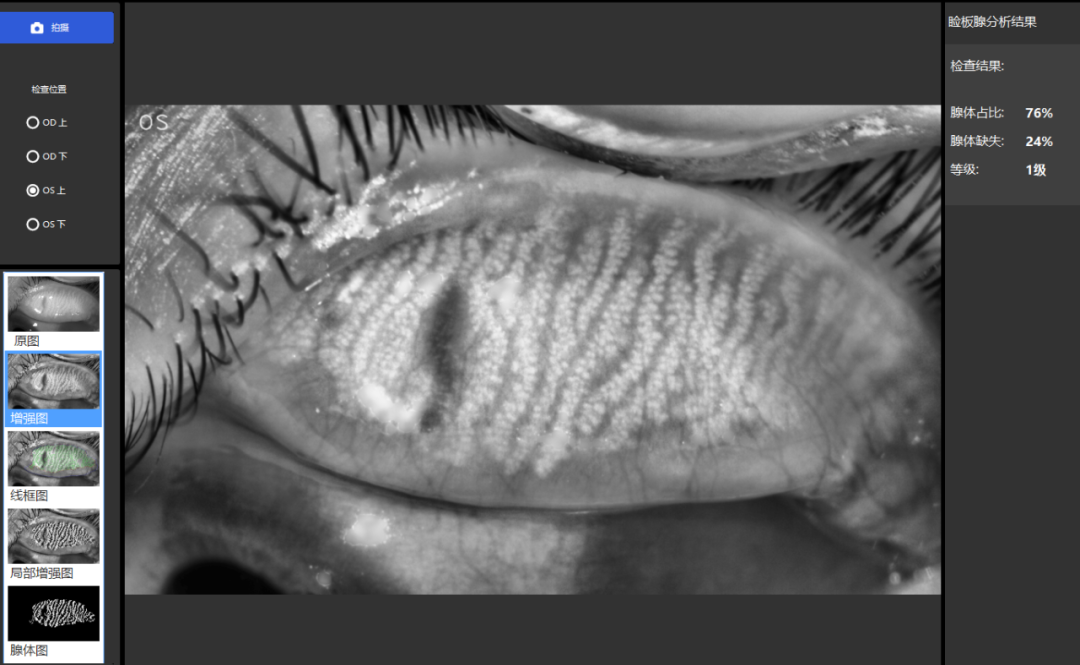

泪膜破裂时间(BUT) 人们每一次眨眼,就会有一层泪膜均匀平铺在眼睛表面。如果正常持续眨眼,泪膜就会保持完整;相反,如果保持不眨眼,泪膜就会破裂,角膜表面会出现干燥斑。因此,从眨眼到泪膜第一次破裂之间的时间间隔即为:泪膜破裂时间(BUT)。泪膜破裂时间大于或等于10秒为正常,当泪膜破裂时间小于10秒,就属于泪膜不稳定的异常,存在干眼症状嫌疑。 泪河高度测量(TMH) TMH主要是测量泪液与睑缘交接处形成的内凹形弧高度,因为此处泪液储留高度间接反映了泪液的分泌量。一般来说,当泪河高度过低,例如:低于0.2mm,就属于异常情况,有可能存在干眼症。 睑板腺功能检查 睑板腺就是位于上下眼皮里的腺管,主要负责油脂分泌。当睑板腺功能异常,油脂就不能正常分泌,泪膜中缺少脂质层,泪液蒸发速度会加快,从而导致干眼。因此,EYESIS干眼综合检查仪利用红外线成像技术对睑板腺形态、开口、腺体分泌物等进行可视化检查是否有异常,是一种评估睑板腺形态改变的客观检查方法。 脂质层厚度检查 脂质层的作用是防止泪液蒸发。正常脂质层色彩较丰富,流动较为缓慢,异常脂质层色彩淡,呈灰白色,流动较快。一般认为脂质层的厚度是0.1μm,也就是脂质层厚度≥100nm是正常的。脂质层厚度越薄,睑板腺功能障碍的可能性越大,如果脂质层厚度≤60nm,则有90%的概率存在干眼症。 荧光角膜染色 角膜、结膜上有损伤或溃疡者,在荧光灯照射下会呈现黄绿色着色。因此,医生在结膜囊内滴入少量荧光素钠,来观察角膜是否存在病变情况。 除了以上五项检查外,还有不完全眨眼、眼红分析、WTW距离分析、OSDI评分、螨虫检查等检查项目,这些检查能够直观、形象地显现眼表结构及功能情况,帮助医生更快速、更准确的发现引起眼干的问题所在。当然,以上仅为干眼诊断的辅助手段,最终诊断需要眼科医生结合临床来判断。